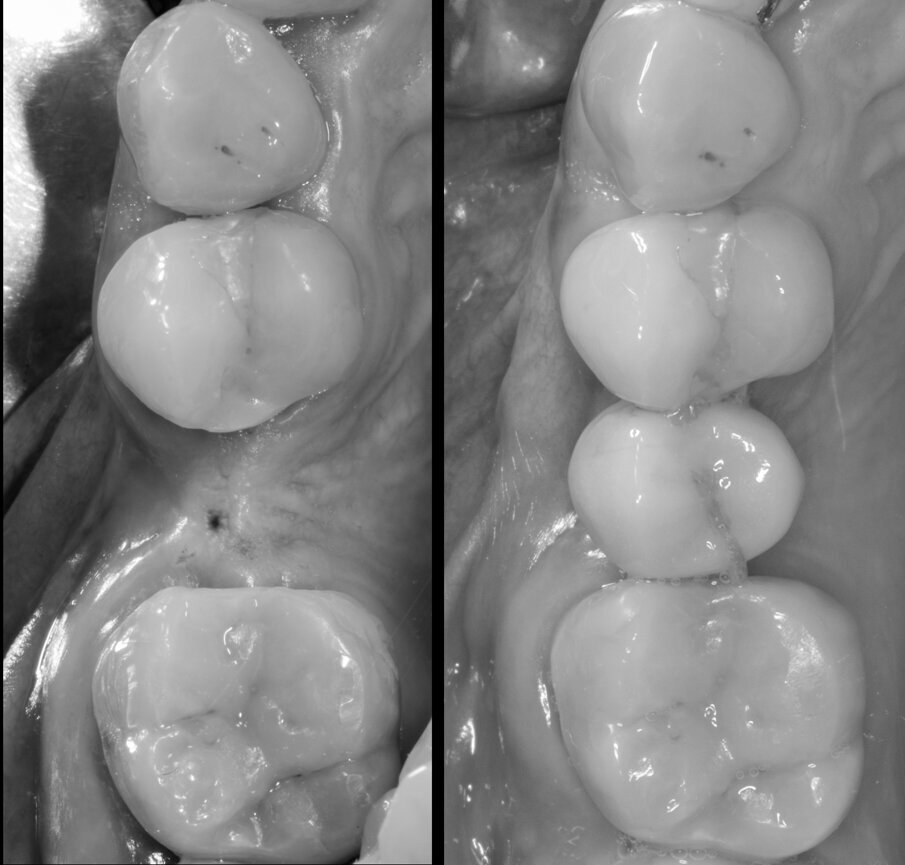

Viene inserito nel centro della cresta neoformata un impianto osteointegrato Neoss Tapered 4.0 x 13 mm con torque di inserimento di 60 Ncm e ISQ 80 (Figg. 22-24). La rigenerazione ossea crestale permette di inserire l’impianto in una posizione protesicamente guidata e con 2 mm di tessuto osseo vestibolare; questa situazione migliora la prevedibilità della riabilitazione implanto-protesica29-33. Dopo 2 mesi di provvisorizzazione si cementa il manufatto protesico definitivo (Figg. 25-28). Il controllo clinico e radiologico a 6 anni (Figg. 29, 30) mostra la stabilità dei tessuti molli e dell’osso perimplantare. Il confronto tra baseline e 6 anni dalla riabilitazione protesica evidenzia la stabilità nel tempo della rigenerazione volumetrica crestale (Fig. 31).

Fig. 29 - Controllo clinico a 6 anni.

Fig. 31 - Confronto tra baseline e 6 anni da riabilitazione implanto protesica.